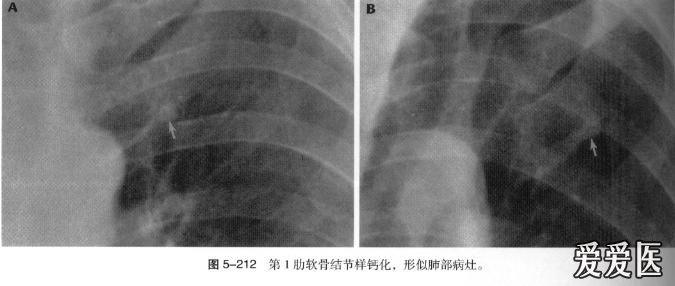

肋骨的正常变异,很容易误诊的

图片尺寸675x286